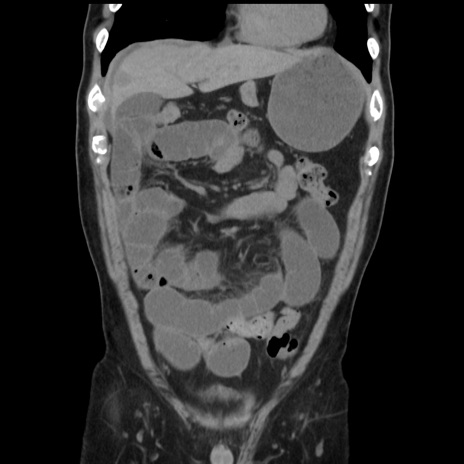

症例16(冠状断像)

【症例】 70歳代男性

【主訴】 腹痛、嘔吐

【現病歴】 約1ヶ月前より間欠的に腹痛と嘔吐あり、当院消化器内科を受診したところCTで多発する肝臓のLDAを指摘され、精査中であった。以降は消化器症状は安定していたが、2日前より嘔気と腹痛があり、同日より排便・排ガスが消失した。改善認めず、 本日、救急外来を受診した。

【身体所見】意識清明・会話良好、BT 36.3℃、BP 127/80mmHg、 P 80bpm、腹部:膨満あり、平坦・軟、上腹部正中および下腹部正中に圧痛あり、反跳痛なし、筋性防御なし。

【データ】WBC 7200、CRP 0.77